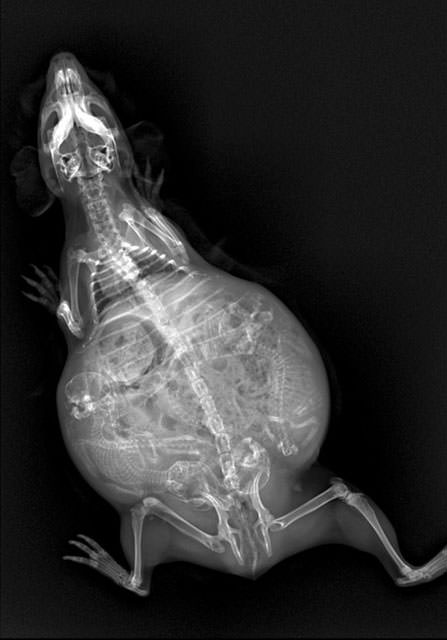

İnsanların ultrason görüntülerini görmeye hepimiz alışkınız. Ancak hamile hayvanların ultrason görüntüleri sizleri çok şaşırtacak.Kaplumbağa

İnsanların ultrason görüntülerini görmeye hepimiz alışkınız. Ancak hamile hayvanların ultrason görüntüleri sizleri çok şaşırtacak.